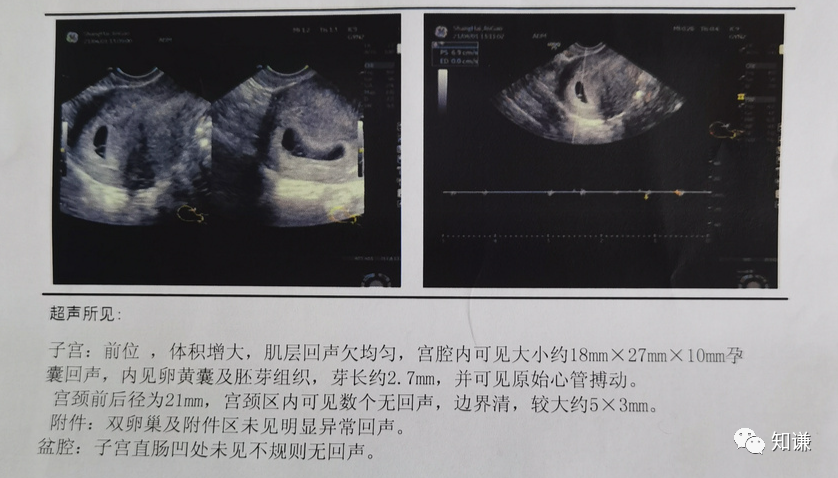

“赶紧去做个检查吧,万一宫外孕什么的就得打掉了。”

就这样我拿到了人生中最特别的一份B超报告,看到了热乎乎的胎心胎芽,原来人类幼崽的雏形就长这样啊~